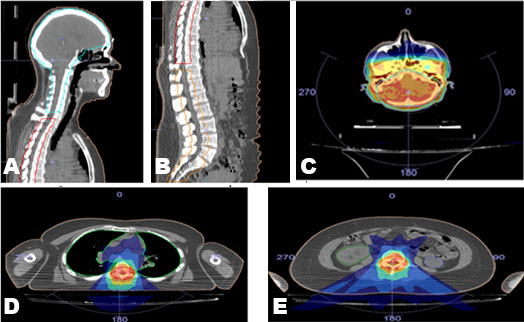

He remained without evidence of recurrent melanoma for the next three years, until routine surveillance positron emission tomography/computed tomography (PET/CT) demonstrated a new left lower lobe pulmonary nodule, the biopsy of which showed recurrent melanoma. He was started on nivolumab 240 mg every two weeks. During cycle 12 (his sixth month of treatment), he developed bilateral swollen flexor tendons to varying degrees of all fingers of his hands along with substantial accompanying tenderness and pain interfering with grasping objects, eating, and writing. He was able to perform activities of daily living (ADLs), such as feed and dress himself, though with significant discomfort. These symptoms rapidly developed over about one week. He could make a fist but could not relax it afterward due to severe pain in the palmar aspect of his hands. There was also erythema of the overlying skin (Figure 1). His fingers were otherwise not swollen, and he had no rheumatoid changes to the joints of his hands. Prior to onset of symptoms, he denied any trauma or medication changes. He had no medical history of auto-immune disorders, tendinopathies, osteoarthritis, soft tissue disorders, or chronic pain within his hands. He had no clinical evidence of infection. He had no other side effects other than chronic sequelae from his baseline COPD (for which he was not receiving oral or inhaled corticosteroids). His physical examination was normal. Considering the known association of nivolumab inducing soft tissue inflammation (and the patient having no similar past medical issues), nivolumab was held for two two-week cycles (about one month). During this period the swelling and pain in his hands greatly improved with slight residual pain in the flexor tendons and skin erythema (Figure 2), but he regained baseline function of his hands. Given the severity of his presenting symptoms, this irAE was considered Grade 3 of 5; i.e., affecting more than one finger or tendon; interfering with, but not preventing or limiting ADLs, and not requiring hospitalization or urgent intervention by Common Terminology for Adverse Events (CTCAE) Version 5.

Figure 1: Photo of the patient’s left hand and treatment-related tendon inflammation prior to delaying treatment with nivolumab.

Figure 2: Photo of the patient’s left hand after delaying nivolumab for one cycle (two weeks).